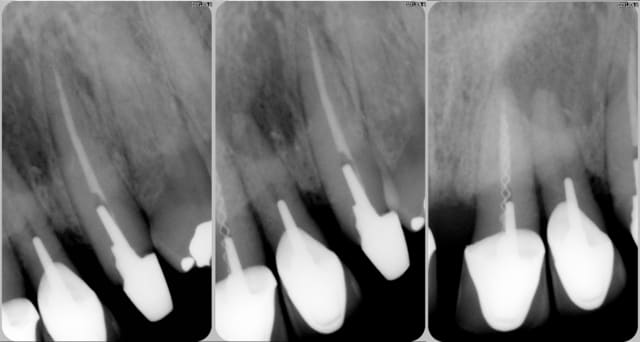

Motif de consultation de ce patient, vu en première consultation ce jour: CCM sur 23 avalée.

Un cliché.

Tiens, y a rien dans 22... Nouveau cliché.

Tiens, ya du monde dans 21... Nouveau cliché.

Tu remarqueras que seule la dent qui contient le lentulo n'a pas de problème...))))

et puis t'as une belle image apicale sur la 22...même que vu la taille, je pense qu'on peut même commencer de parler de kyste...

Non, il y a deux lentuli.

Pour sortir un lentulo : introduire un 2ème lentulo et tournez à l'envers .